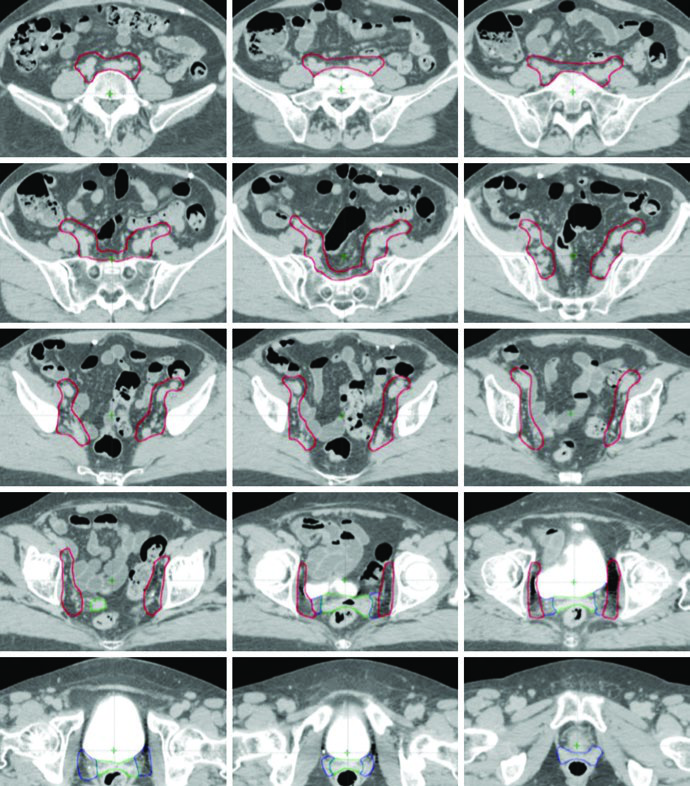

Postoperative delineation for cervical and uterine cancer patients utilizes multiple CTVs — CTV1, CTV2, and CTV3 — allowing anisotropic CTV-to-PTV expansions. Each component has a distinct anatomic role and margin, as defined in the TIME-C randomized clinical trial.

Target Volume Definitions: CTV1, CTV2, and CTV3

| Volume | Definition | CTV-to-PTV Expansion |

|---|---|---|

| CTV1 | Vaginal cuff, including fat and soft tissue anterior and posterior to the cuff between the bladder and rectum | 15 mm |

| CTV2 | Paravaginal/parametrial tissues, proximal vagina (excluding the cuff) | 10 mm |

| CTV3 | Common iliac, external iliac, and internal iliac nodal regions — pelvic vessels + 7 mm expansion (excluding bone, muscle, and bowel), soft tissues between internal and external iliac vessels, presacral nodes (soft tissues anterior to S1-S2, minimum 1.0 cm). Upper extent: 7 mm inferior to L4-5 interspace. Lower extent: superior aspect of femoral head | 7 mm |

Source: Target Volume Delineation and Field Setup, 2nd Edition (Table 20.1)

Regarding CTV1, the anterior portion of the uterosacral ligament is removed during radical hysterectomy. Consequently, the mesorectal fascia serves as a surrogate structure for the posterior border of the vaginal cuff and parametrium CTV. Vaginal boost can be considered in patients at higher risk for recurrence due to cervical stromal invasion, supracervical hysterectomy, extensive LVSI, or extensive vaginal involvement.

In endometrial cancer patients, CTV3 is modified to include the presacral region when cervical stromal invasion is present. When pathologic involvement of para-aortic or high common iliac nodes is confirmed, extended pelvic-para-aortic fields are used, with the upper border of the CTV extending to the T12-L1 or L1-L2 interspace, or the renal vasculature.

For cases with distal one-third vaginal involvement, inguinal nodes should be contoured continuously from the external iliac nodes to 2 cm caudal to the saphenous-femoral junction.

Final PTV Composition

PTVs are created for each CTV with different margins — 15 mm for CTV1, 10 mm for CTV2, and 7 mm for CTV3 — reflecting the degree of internal organ motion and setup uncertainty for each component. The final PTV for treatment planning is generated by combining the individual PTVs: PTV = PTV1 ∪ PTV2 ∪ PTV3.

When using the ITV approach, CTV1 and CTV2 should be contoured on both empty and full bladder scans and fused to generate the ITV. A 7 mm expansion on the ITV generates the PTV, which is combined with PTV3 for the final PTV. This strategy is particularly important because the vaginal cuff and paravaginal tissues undergo significant displacement with bladder filling variations.